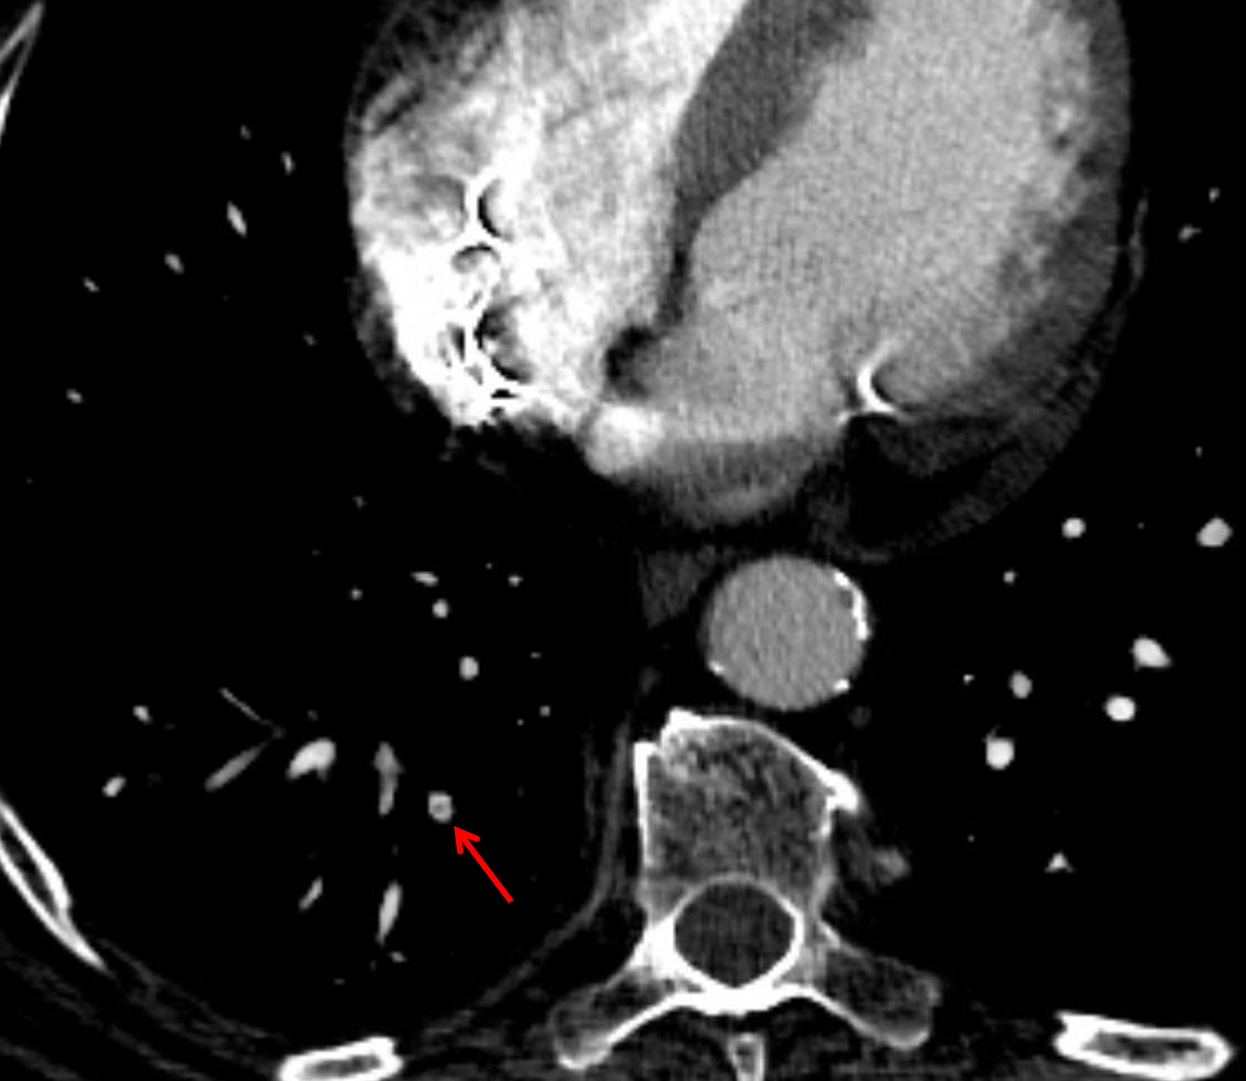

Outpouching arising from the inferior wall of the left ventricle most suggestive of a false aneurysm (pseudoaneurysm).